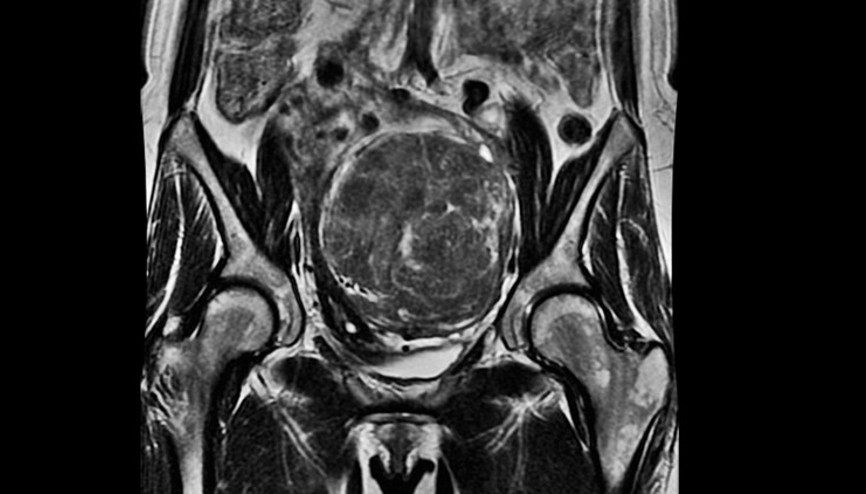

#Rahim MiyomlarıTokat'ta kilo aldığını düşünerek doktora başvuran Güler Kaymak isimli kadının karnından ameliyatla çıkartılan 5 kilo ağırlığında 40 santimetre boyunda miyom, görenleri şaşırttı. Kaymak'ın karnının gebe karnı büyüklüğünde olduğunu söyleyen doktoru "Nefes alamıyor, zor yürüyordu. Ameliyatla yaklaşık 40 santimetre boyunda 5 kilo ağırlığında adeta böyle tabiri caizse dikey mimari gibi büyümüş çam ağacı şeklinde yüzlerce miyomdan oluşan bir kitleyi başarılı bir şekilde çıkardık" ifadelerini kullandı

#Serkan KızılbayırKars'ta şiddetli karın ağrısı, idrar kaçırma ve kabızlık şikayetiyle Kafkas Üniversitesi Sağlık Araştırma ve Uygulama Hastanesi'ne giden 5 çocuk annesi Sebiye Topkaya'nın (65) karnından 30 santimetre genişliğinde 6 kilo ağırlığında kitle çıkarıldı.

#Yumurtalık KanseriAdana’da yaşayan, 20 yıldır çocuk sahibi olma hayali kuran ve karın ağrısı şikayeti çeken G.D.’nin (40), Diyarbakır’da özel bir hastanede yapılan tetkiklerde karnında büyük bir kitle olduğu tespit edilince ameliyata alındı. Karnından 10 kilo ağırlığında ve 30 santimetre çapında kitle çıkarılan G.D.’nin operasyonunu gerçekleştiren Kadın Hastalıkları ve Doğum Uzmanı Opr. Dr. Fuat Zaman, “Ameliyatımız başarıyla gerçekleşti. 1-2 ay sonra hasta iyileşince çocuk tedavisi yapacağız” dedi.

#DiyarbakırAdana’da yaşayan, 20 yıldır çocuk sahibi olma hayali kuran ve karın ağrısı şikayeti çeken G.D.’nin (40), Diyarbakır’da özel bir hastanede yapılan tetkiklerde karnında büyük bir kitle olduğu tespit edilince ameliyata alındı. Karnından 10 kilo ağırlığında ve 30 santimetre çapında kitle çıkarılan G.D.’nin operasyonunu gerçekleştiren Kadın Hastalıkları ve Doğum Uzmanı Opr. Dr. Fuat Zaman, “Ameliyatımız başarıyla gerçekleşti. 1-2 ay sonra hasta iyileşince çocuk tedavisi yapacağız” dedi.